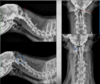

identify issue

Atlantoaxial instability blue circle and arrow = normal red arrows point to abnormalities